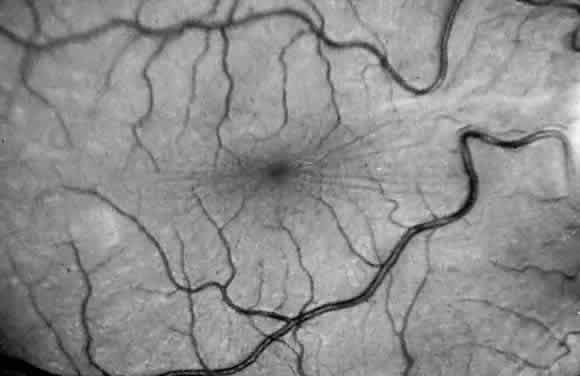

Corneal clouding (Fig. 10), hyperopic astigmatism, and a mild retinopathy with surface-wrinkling maculopathy (Fig. 11) appear to be the constant ocular triad.75 Some patients have retinal vascular tortuosity, optic nerve head swelling (Fig. 12), visual field defects, and abnormalities in color vision. Visual complaints are uncommon.

Fig. 10. Mild corneal clouding in a child with mucolipidosis III. (Traboulsi E, Maumenee I: Ophthalmologic findings in mucolipidosis III. Am J Ophthalmol 102:529, 1986)

Fig. 11. Surface-wrinkling maculopathy in a patient with mucolipidosis III. (Traboulsi E, Maumenee I: Ophthalmologic findings in mucolipidosis III. Am J Ophthalmol 102:529, 1986)

Fig. 12. Optic nerve head swelling in a patient with mucolipidosis III. (Traboulsi E, Maumenee I: Ophthalmologic findings in mucolipidosis III. Am J Ophthalmol 102:529, 1986)